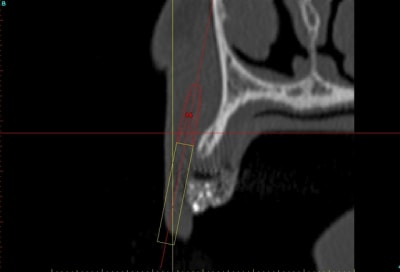

J'aurais bien aimé avoir des coupes radio avant/après.

C'est possible?

voilà, j'ai trouvé 5 mn...

le projet simplant est théorique, ça ne correspond pas à ce qui sera posé, c'était pour étude.

Il n'y avait pas grand chose en effet.